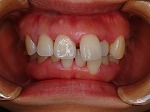

◆オールセラミック修復

→